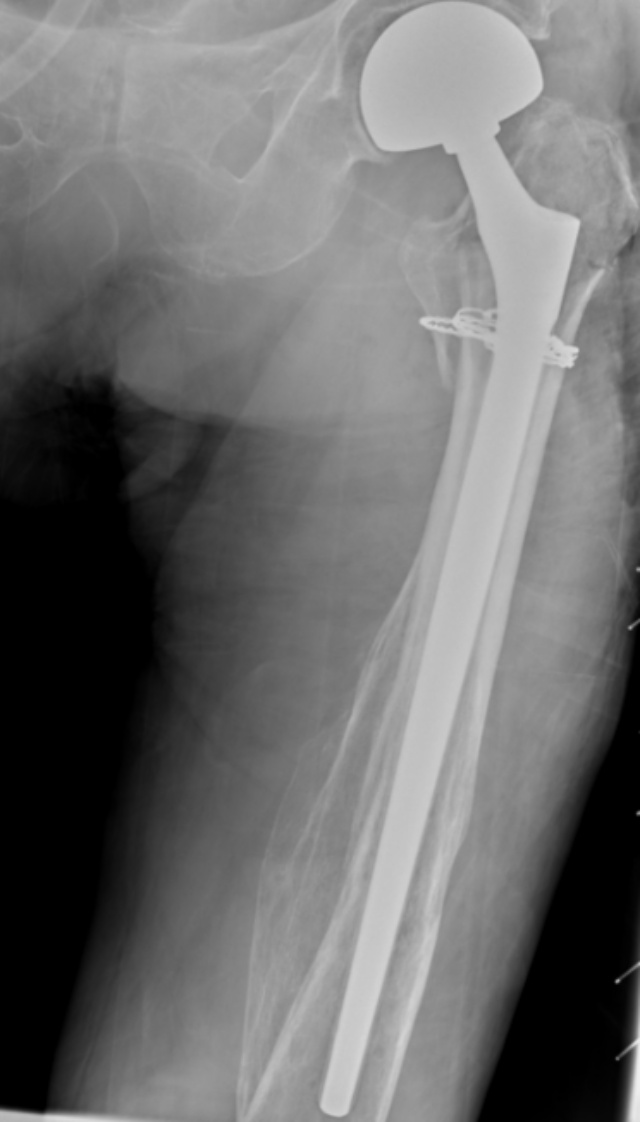

典型病例影像学表现见图1~10。图1为86岁女性右侧股骨转子间骨折(Evans Ⅲ型)患者,术前X线示骨折断端部分错位,术后X线示骨折位置可以及假体位置良好;图2显示了一名81岁男性患者,诊断为左侧股骨转子间骨折,类型为Evans V型,合并股骨干陈旧性骨折。患者接受了生物型加长柄半髋关节置换手术,并进行了股骨近端的钢丝捆扎内固定。术后X线示假体位置良好,股骨近端予钢丝捆扎固定;图3为87岁女性左侧股骨转子间骨折(Evans V型)患者,术后X线示假体位置良好,股骨大小转子骨折位置可,钢丝捆扎固定在位有效;图4为75岁女性左侧股骨转子间骨折(Evans V型)患者,术前X线示左侧股骨转子间骨折PFNA术后、骨折未愈合、内固定断裂。术后假体匹配良好,股骨近端钢丝内固定稳定可靠;图5为75岁男性左侧股骨转子间骨折(Evans IV型)患者,术后股骨大转子出现轻度位移,假体位置正常。图6为87岁男性左侧股骨转子间骨折(Evans V型)患者,给予DAA入路加长柄半髋关节置换,术前X线片,清晰地显示出左侧股骨转子间的骨折情况,术后X线影像,显示股骨的大小转子骨折位置良好,钢丝内固定装置在位稳定,假体位置良好;图7为77岁女性右侧股骨转子间骨折(Evans V型)患者,术前X线片显示右侧股骨转子间存在骨折且股骨大小转子均有累及和移位,术后X线片显示股骨小转子轻度移位,内固定装置位置稳定,假体位置良好;图8为70岁男性左侧股骨转子间骨折(Evans III型)患者,术前的X线片,清晰地显示了左侧股骨转子间的骨折情况,股骨近端髓腔钙化灶,术后假体位置满意;图9为77岁女性右侧股骨转子间骨折(Evans V型)患者,术前X线片,显示右侧股骨转子间及转子下部位骨折情况。术后假体匹配良好;图10为71岁男性右侧股骨颈骨折(Evans IV型)患者,术前X线片,显示右股骨转子间骨折的情况;术后X线表明股骨的大转子和小转子骨折位置保持良好,内固定装置稳固,术后假体位置正常。

(a) (b)

Figure 10. A 71-year-old male patient with right femoral neck fracture (Evans type IV). (a) Before surgery; (b) After surgery

10. 71岁男性右侧股骨颈骨折(Evans IV型)患者。(a) 术前;(b) 术后